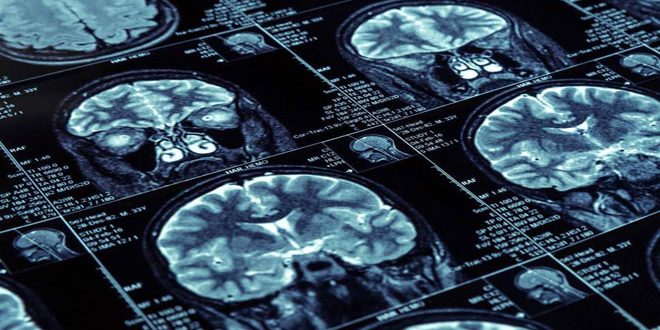

أظهرت دراسة طبية بريطانية حديثة أن الأشخاص الذين يعانون من الوزن الزائد في منطقة الخصر تكون أدمغتهم أصغر من غيرهم.

وأوضحت الدراسة التي نشرتها صحيفة ديلي تلغراف البريطانية بعنوان: البدناء يكون حجم المخ لديهم صغير “أن العلماء توصلوا إلى سبب جديد يجعلنا نعمل على التخلص من الوزن الزائد وذلك لمنع انكماش المخ لدينا”.

وأكدت الدراسة التي أجرتها جامعة لوبورو في لندن أن الوزن الزائد حول الخصر له علاقة بضمور الدماغ وعجز الذاكرة كما أنه يمكن أن يساهم في الإصابة بحالات تراجع مستوى الأداء العصبي مثل مرض الزهايمر.

واعتمدت الدراسة على بيانات أكثر من 9600 شخص في جميع أنحاء بريطانيا يبلغ معدل أعمارهم 55 عاما حيث كان 19 بالمئة منهم يعانون من البدانة ووجدت الدراسة علاقة واضحة بين مؤشر كتلة الجسم وبين قصور واضح في الذاكرة.